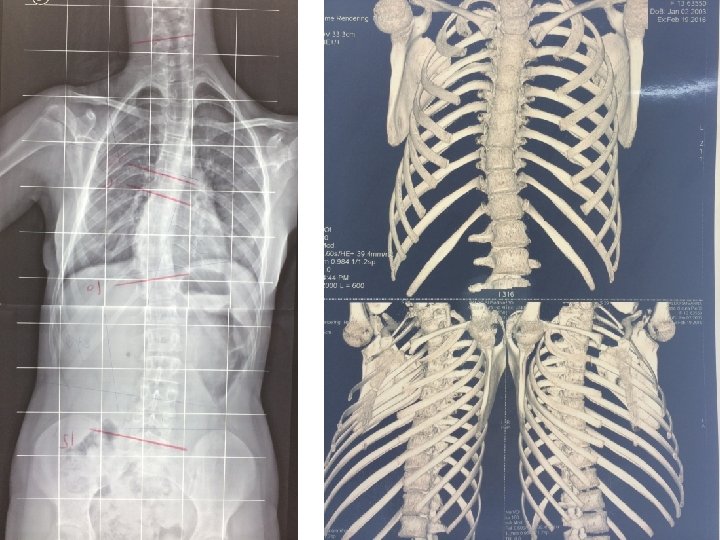

C, F. 12 a. Atresia esofagea

T. S. a. 2 Rx. in A. G. In trazione Su letto di Cotrel Gesso EDF

T. S. 62° Cobb a. 10 + 10 m. Prepubere 8 anni e 10 mesi di trattamento conservativo

T. S. 13 Y +10 M.